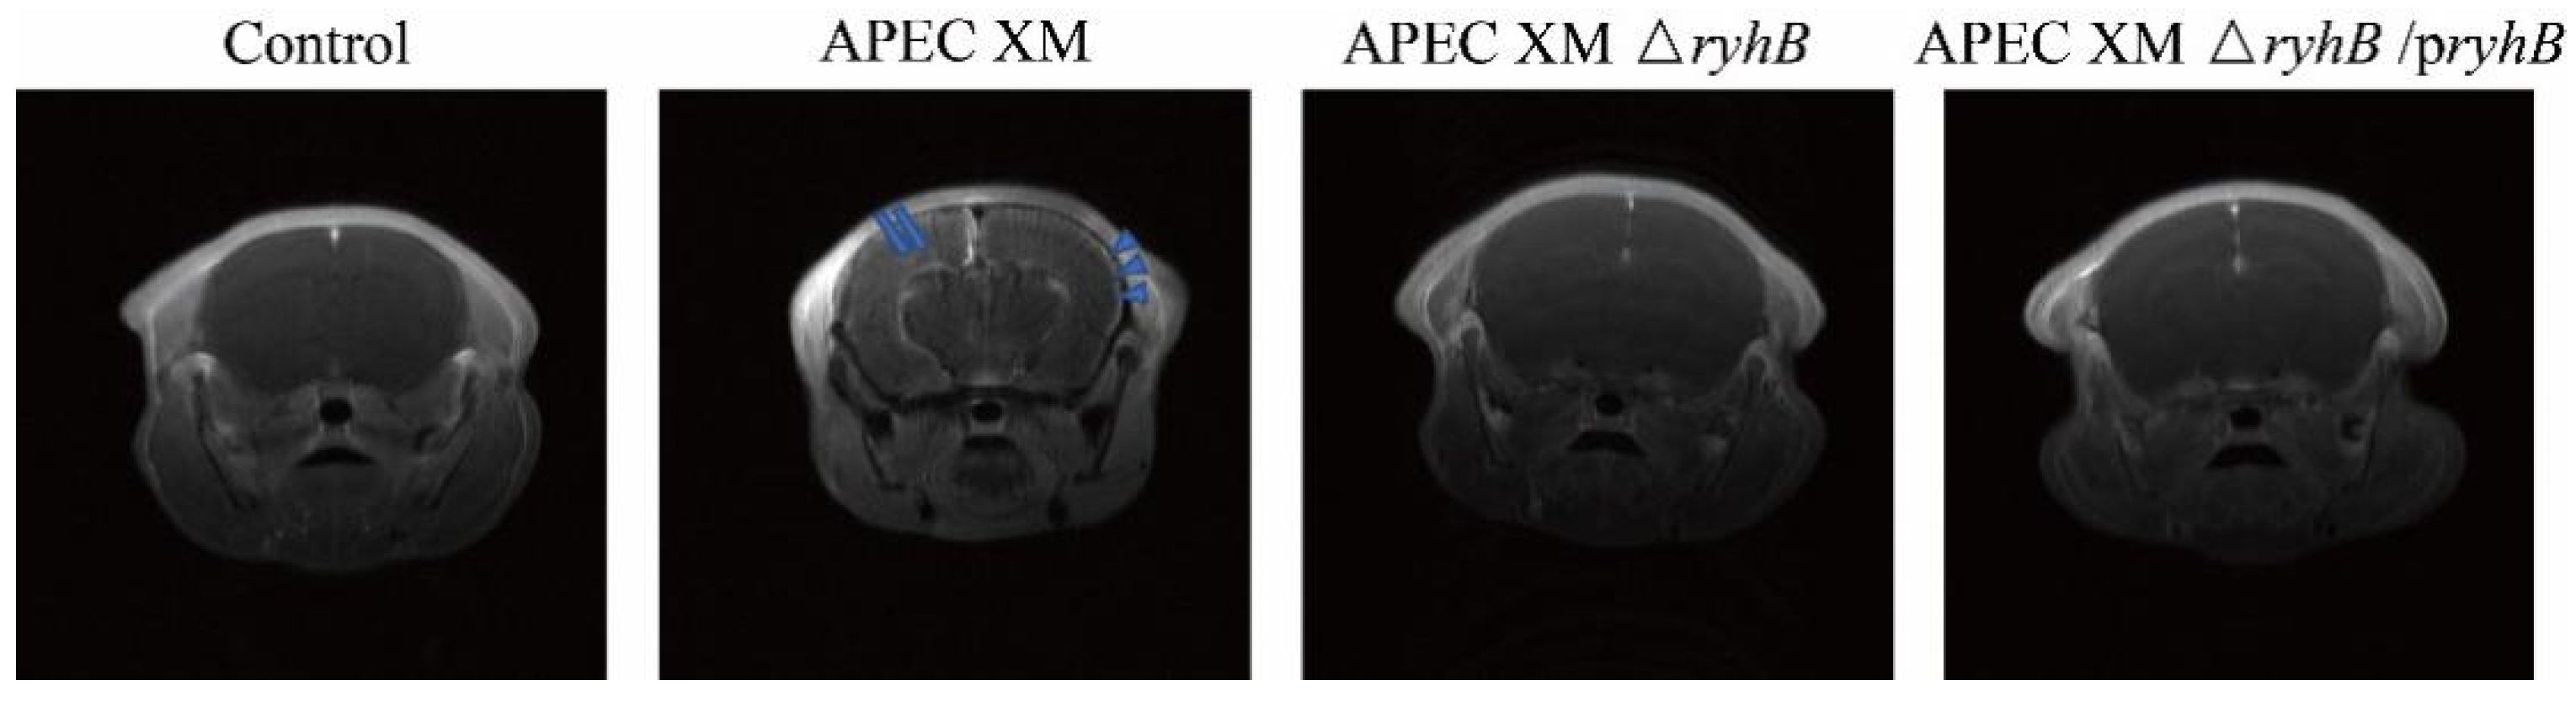

2.6. RyhB Contributes to Brain Lesions of Mice

2.7. RyhB Helped APEC XM to Damage the Integrity of the Blood–Brain Barrier